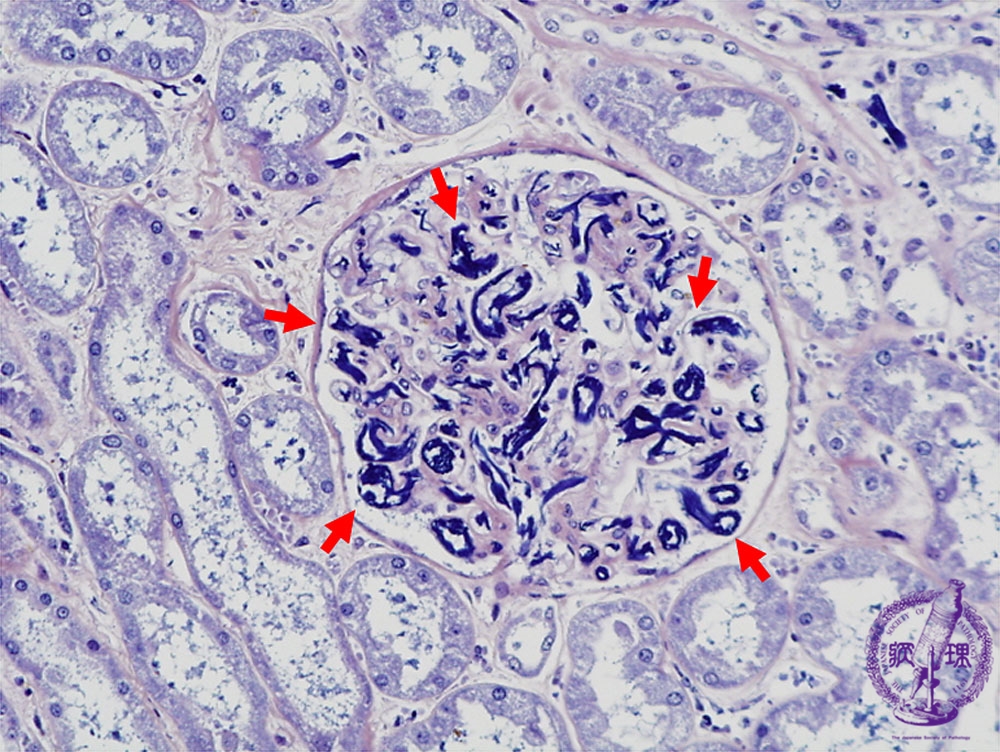

- ★(9)Disseminated intravascular coagulation (DIC)

Microscopic findings (PTAH, high power view): Microthrombi within glomerular capillary lumens are highlighted by PTAH which stains nuclei and fibrin blue (red arrows).

Click the image to see the enlarged image.